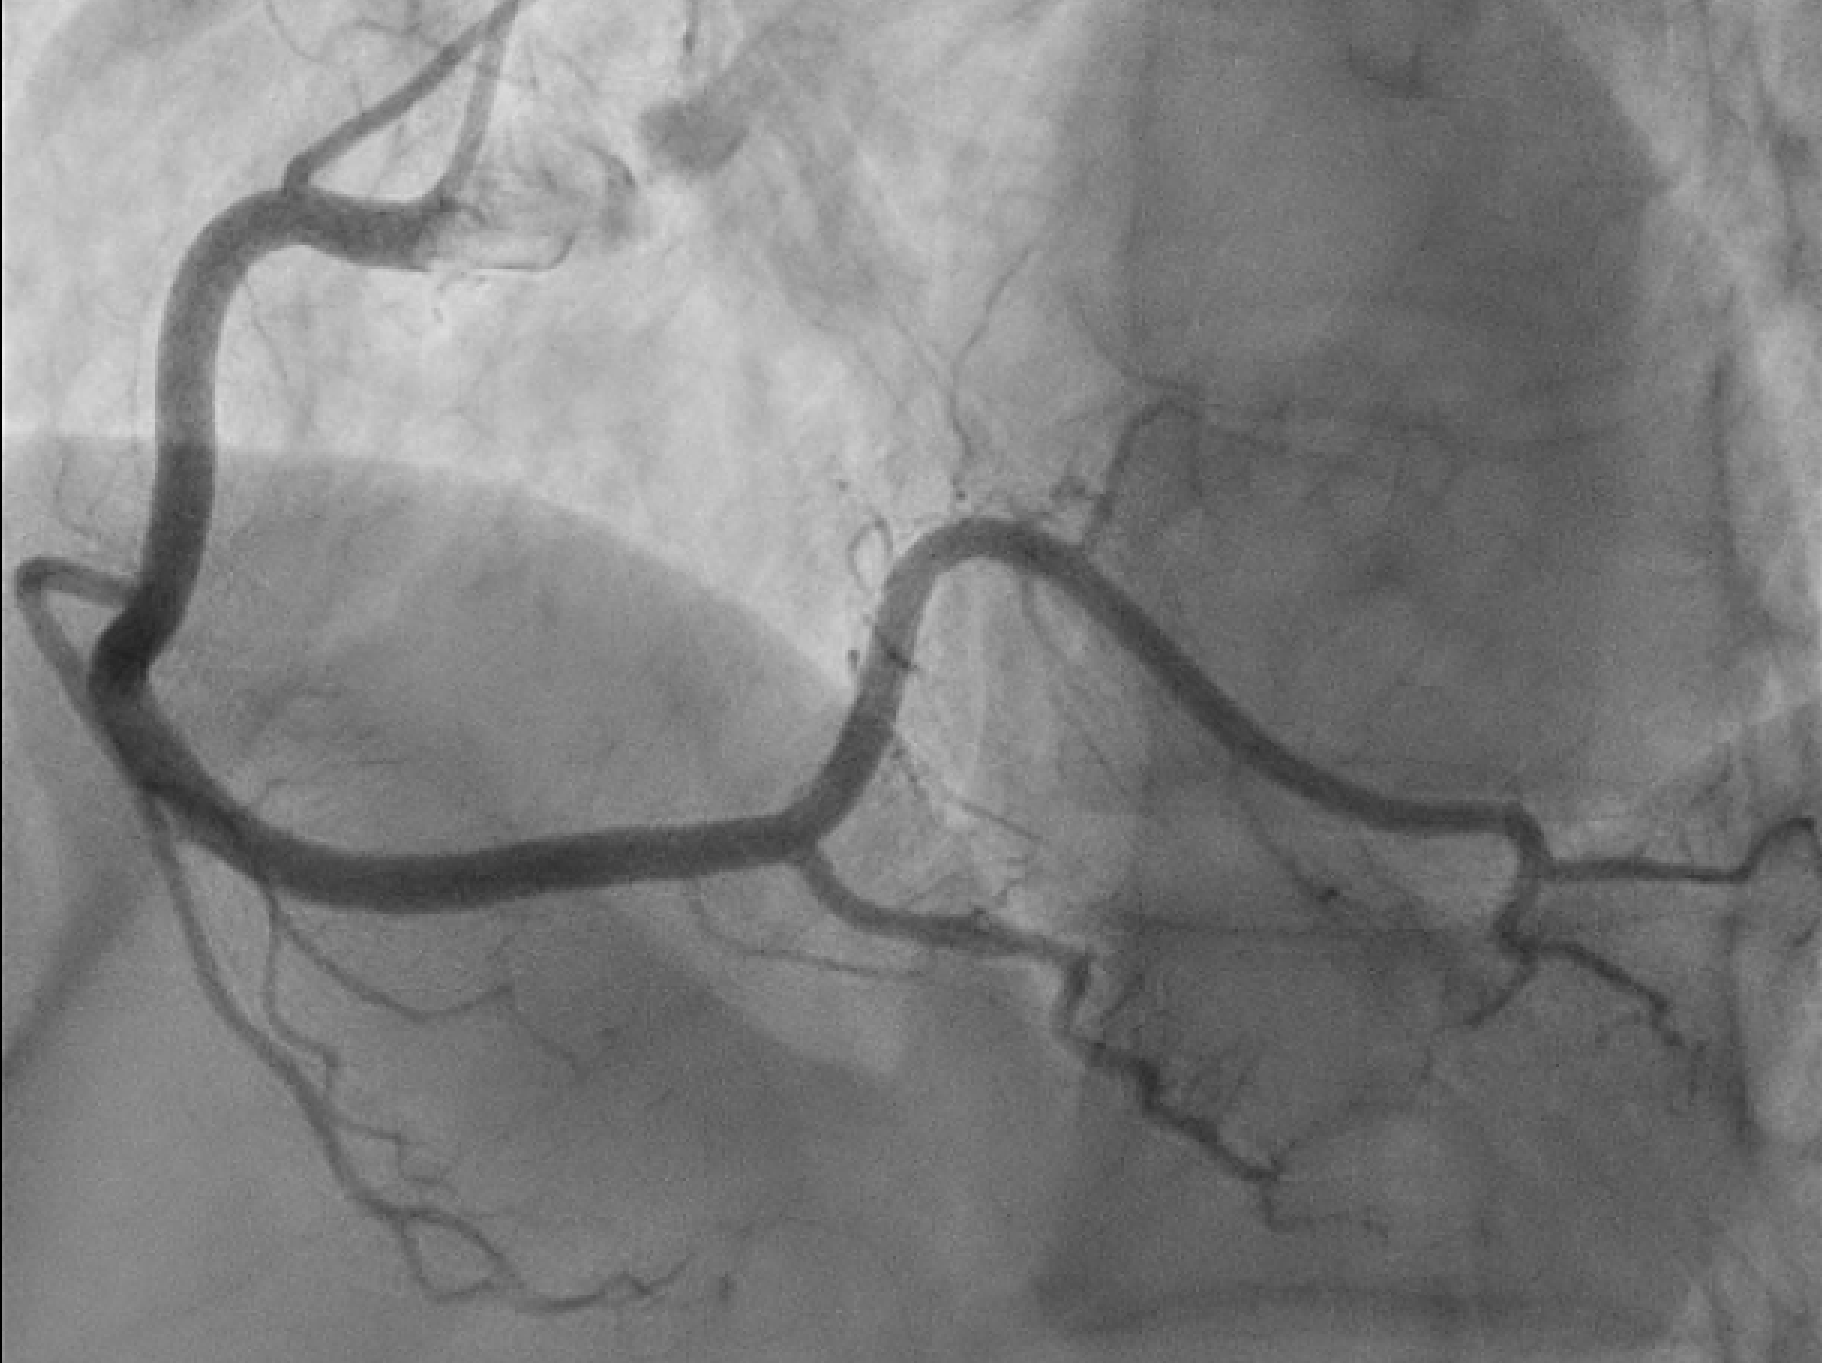

Case Presentation: We have a 63 year old female with a history of spontaneous coronary artery dissection (SCAD) of the left anterior descending artery (LAD) 2 years prior that was found on a left heart catheterization after she presented to the ER with a complaint of chest pain with associated dyspnea. On a physical exam, the patient was in distress with an unremarkable cardiopulmonary exam. EKG was significant for ST elevations in leads II, III, and aVF consistent with an inferior STEMI. She was urgently taken for coronary angiography that showed severe (90%) stenosis of the long segment branch of the right posterior descending artery (RPDA) with pruning of distal branches consistent with SCAD. Initially, the artery had TIMI 1 flow (figure 1) but improved to TIMI 2 flow with intracoronary nitroglycerin administration (figure 2). No increased tortuosity was noted on the angiogram. Echocardiogram done showed an ejection fraction of 60-65%. Her risk factors for metabolic syndrome were optimized. She was monitored closely in the ICU overnight on nitroglycerin infusion with management of chest pain. She was counseled on the benefits of tobacco smoking cessation and the risks of possible SCAD recurring with continued smoking.